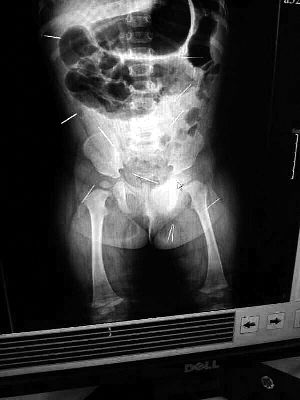

山東聊城11個(gè)月女嬰萱萱(化名)疑似被人以12根鋼針插滿臀部、腹腔等部位,昨天在兒童醫(yī)院會診后,醫(yī)生稱3根針靠近胸腔最危險(xiǎn),首批先行取出,預(yù)計(jì)將在下周二手術(shù)。孩子父母稱孩子一直由家人照顧,自家與他人并無冤怨。山東警方表示正在偵破中,不便透露案情。

“要不是當(dāng)初那幾個(gè)紅點(diǎn),可能到現(xiàn)在我們還不知道孩子身體里有鋼針!”昨天,在兒童醫(yī)院住院處,萱萱爸爸范先生稱,日前原本很愛笑的萱萱突然變得有些焦躁,一抱起來就哭,孩子母親偶然間在萱萱屁股上發(fā)現(xiàn)了幾個(gè)小紅點(diǎn)兒,原以為是蚊蟲叮咬,就醫(yī)結(jié)果卻讓人不寒而栗。“醫(yī)院拍出的片子上,萱萱的體內(nèi)有12根鋼針,插滿臀部、腹腔、骨盆等各個(gè)部位。”范先生介紹,因?yàn)殇撫樢焉钊塍w內(nèi),要是孩子不哭鬧,他們很難發(fā)現(xiàn)。

北京晨報(bào)記者了解到,目前體內(nèi)的12根鋼針多分布在孩子的臀部,一根在腹部,其余3根在胸腔附近,其中一根很接近心臟。“因?yàn)楹⒆犹?,醫(yī)生們害怕取針的時(shí)候?qū)λ斐蓚?,在胸腔附近?針可能會威脅她的生命”。